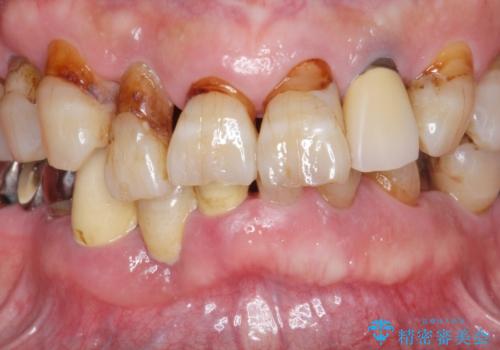

歯周病治療を伴う前歯審美セラミック治療

- 前歯の見た目をなんとかしたい、とセラミック治療を希望され来院されました。

セラミック治療を行う前に歯周病の問題を解決すべく歯周外科を行い歯周ポケットを除去し整備したのちセラミックブリッジ・クラウンの製作を行います。